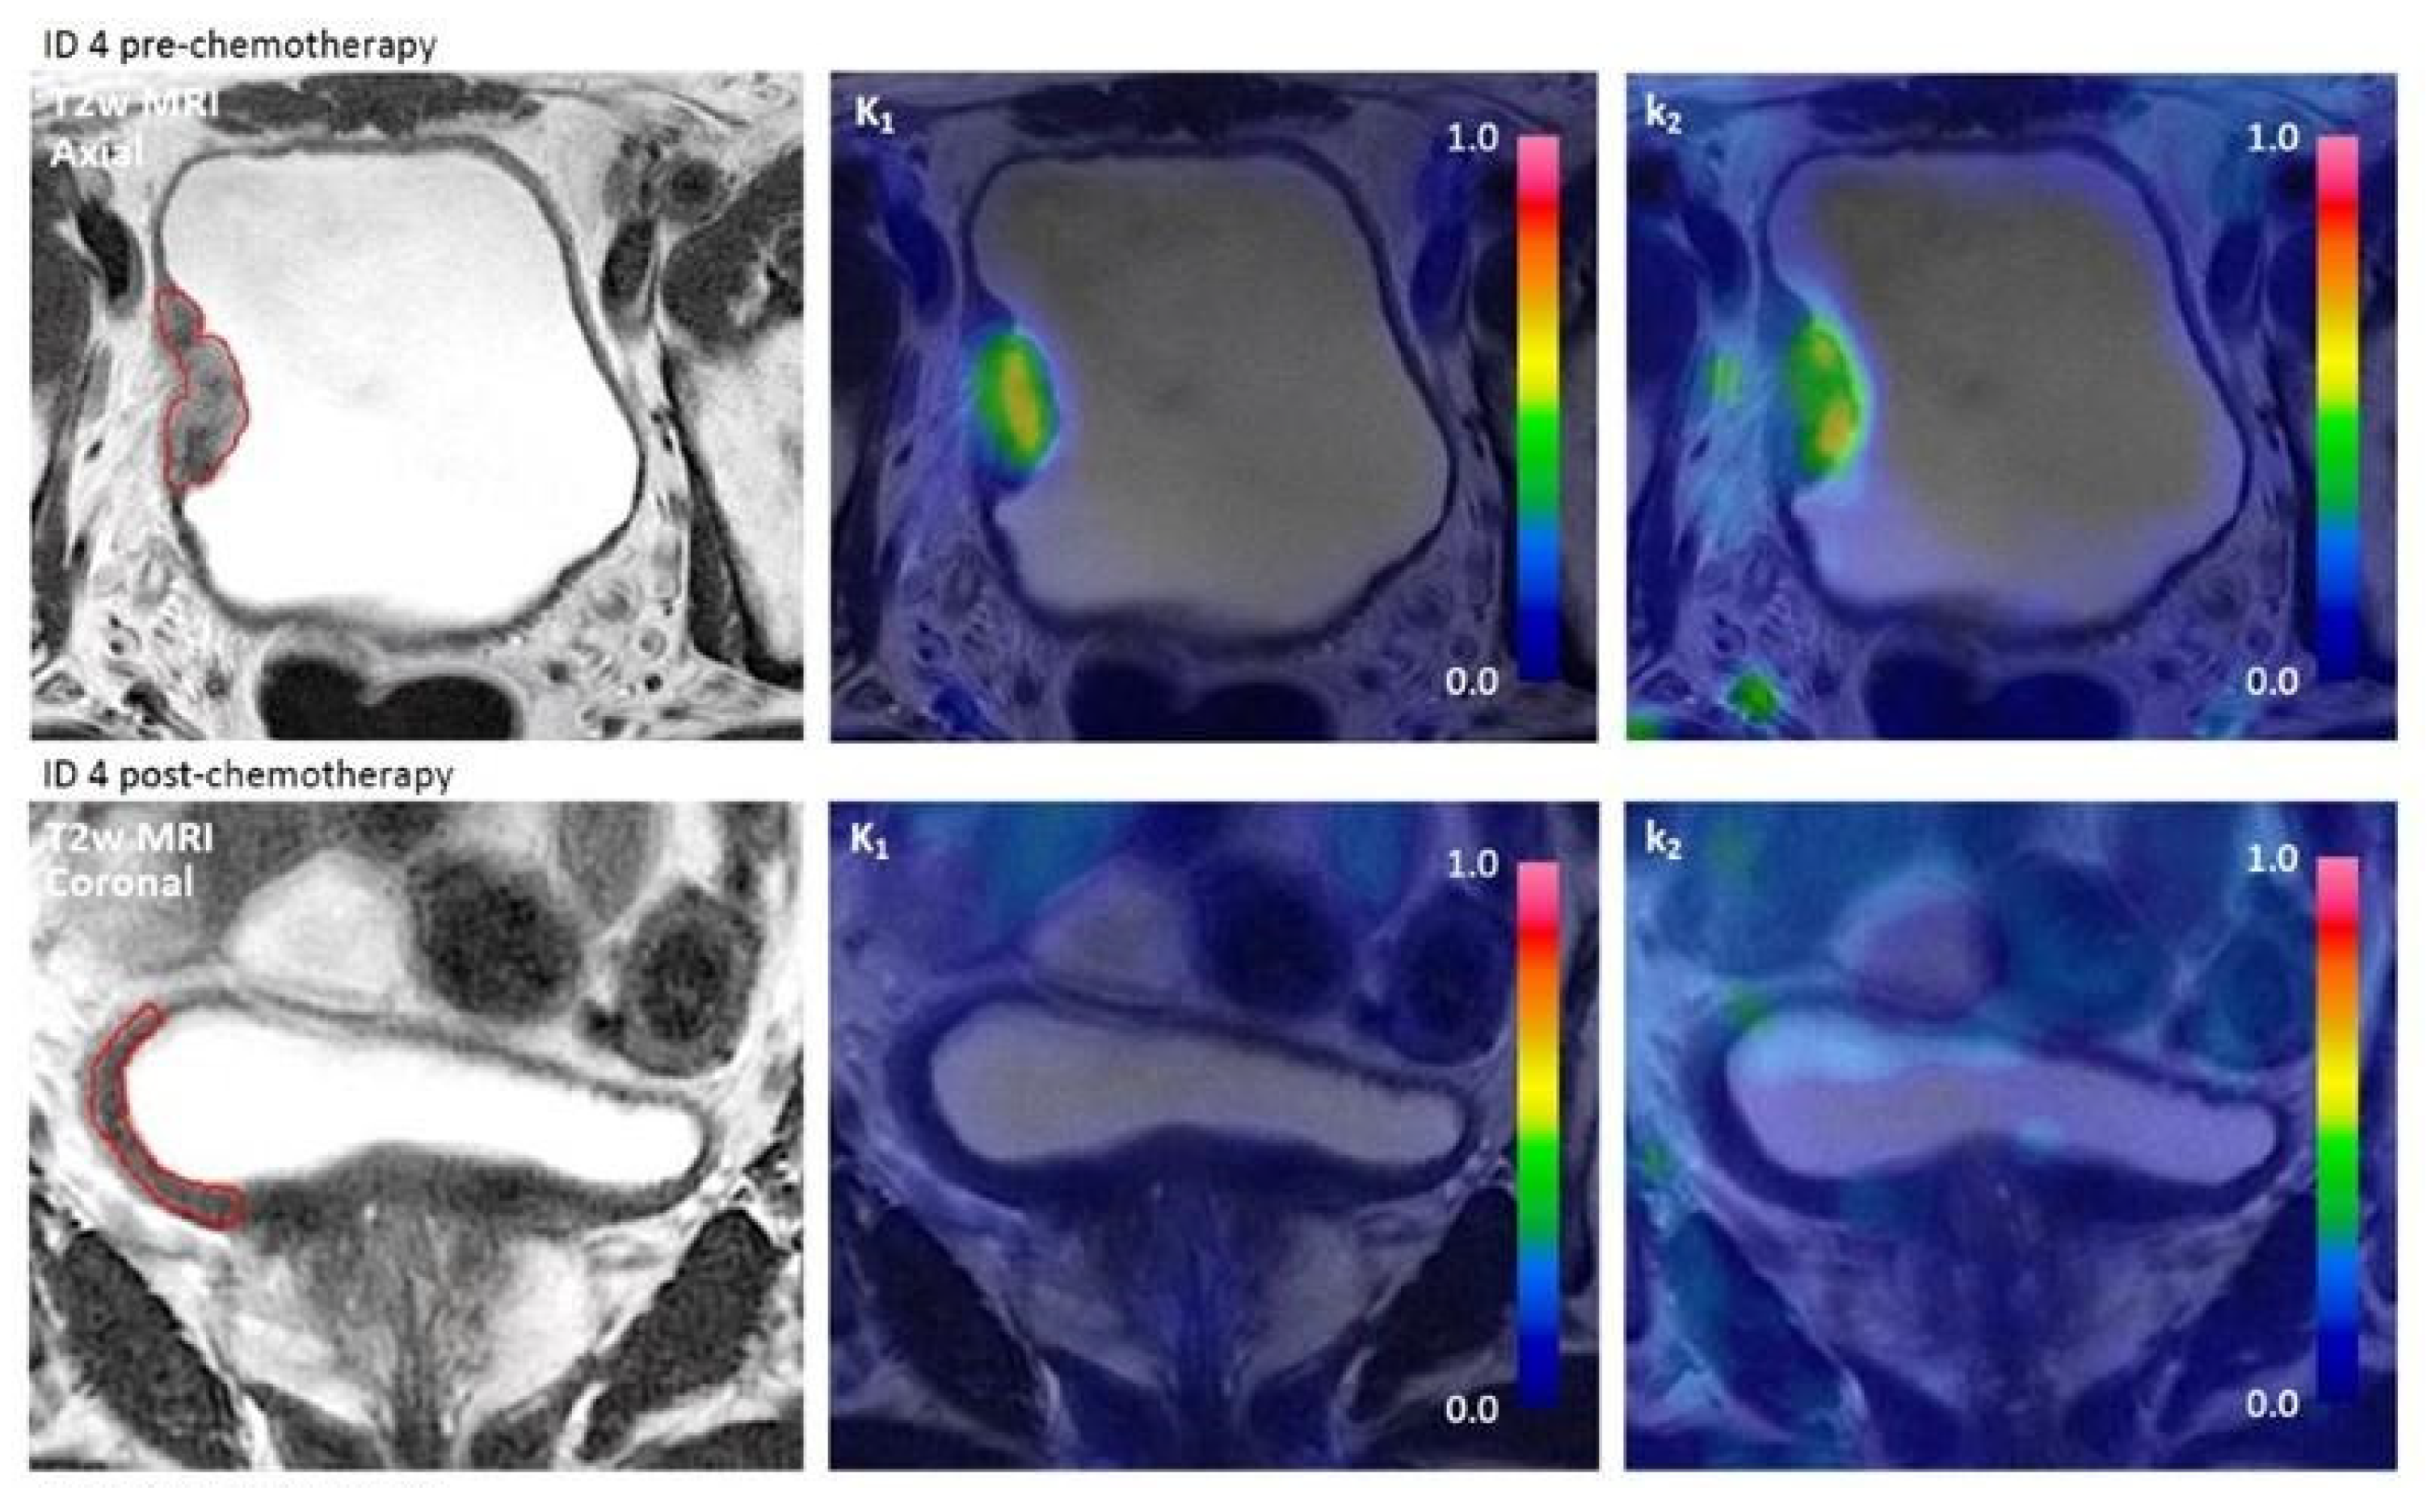

T2-weighted (T2w) MRI and [15O]H2O PET parametric images (K1 and k2) pre- and post-chemotherapy of three study patients. ID 4 had wall thickening on T2w MRI but decreased tumor blood flow (TBF) post-chemotherapy and had ypT1b + Tis. ID 5 had no visible tumor and decreased TBF post-chemotherapy and had ypT0. ID 11 had suspect volume of interest but decreased TBF post-chemotherapy, and patient had ypT0.

The measured decrease in TBF post-chemotherapy could be due to either local response to chemotherapy or time since TURBT, depending on whether the pre-chemotherapy scan showed increased TBF due to inflammatory changes from the TURBT. The pre-chemotherapy scan was performed 20–65 days after TURBT. For ID 5, Figure 2, increased perfusion on the pre-chemotherapy parametric image could resemble sequelae after TURBT; however, PET/MRI was performed 47 days after TURBT, which should be adequate time for healing of the mucosa. For ID 11, the pre-chemotherapy scan was performed 21 days after TURBT and increased perfusion might partly reflect TURBT sequelae.